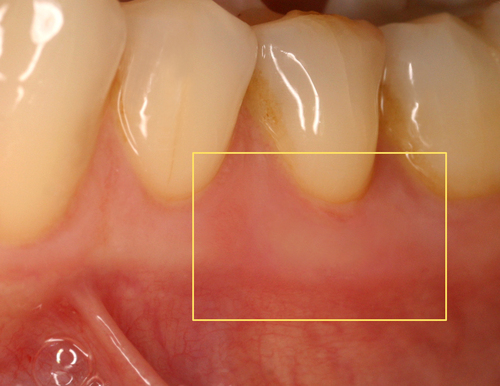

Cette biostimulation qui peut durer plusieurs minutes aboutit en général à une guérison très rapide et indolore des ulcérations gingivales (fig. 22)

Fig.22

Cicatrisation en quelques jours